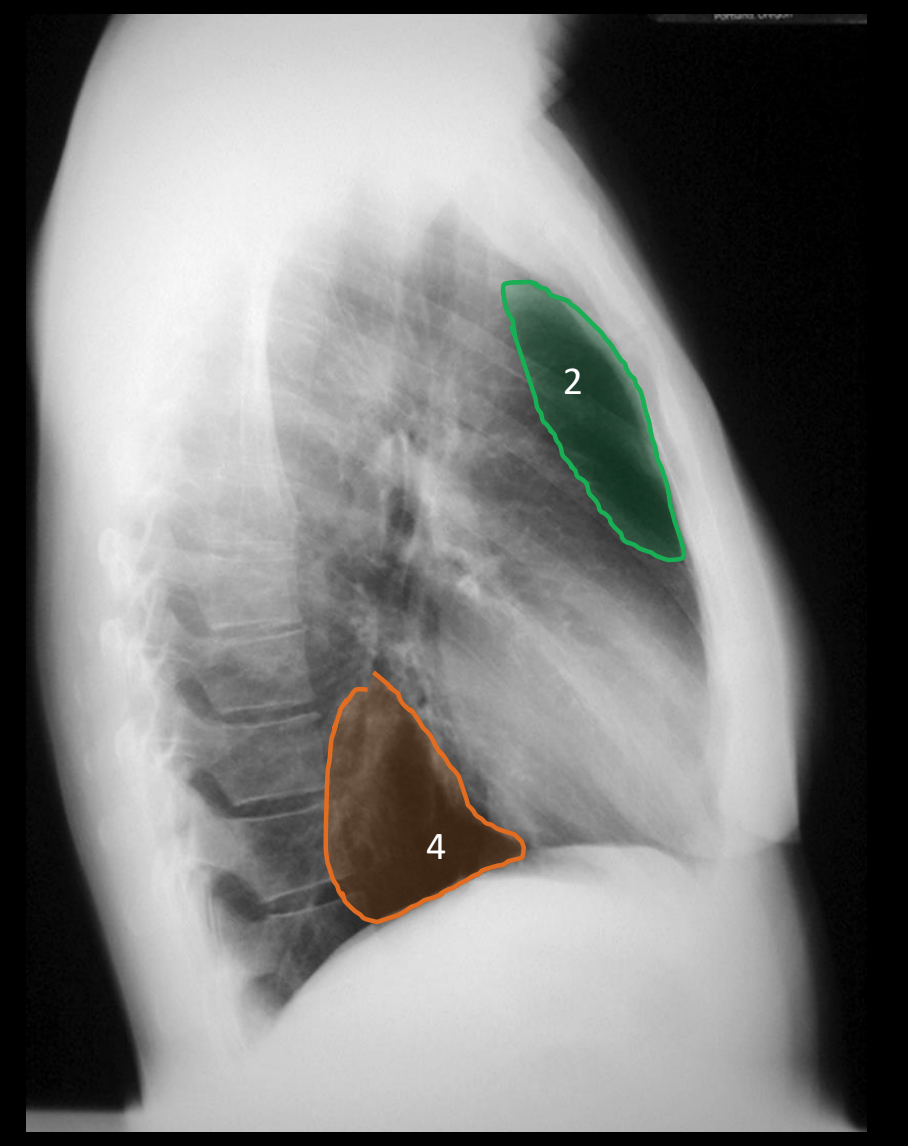

what is 4?

posterior clear space

what is 2?

anterior clear space